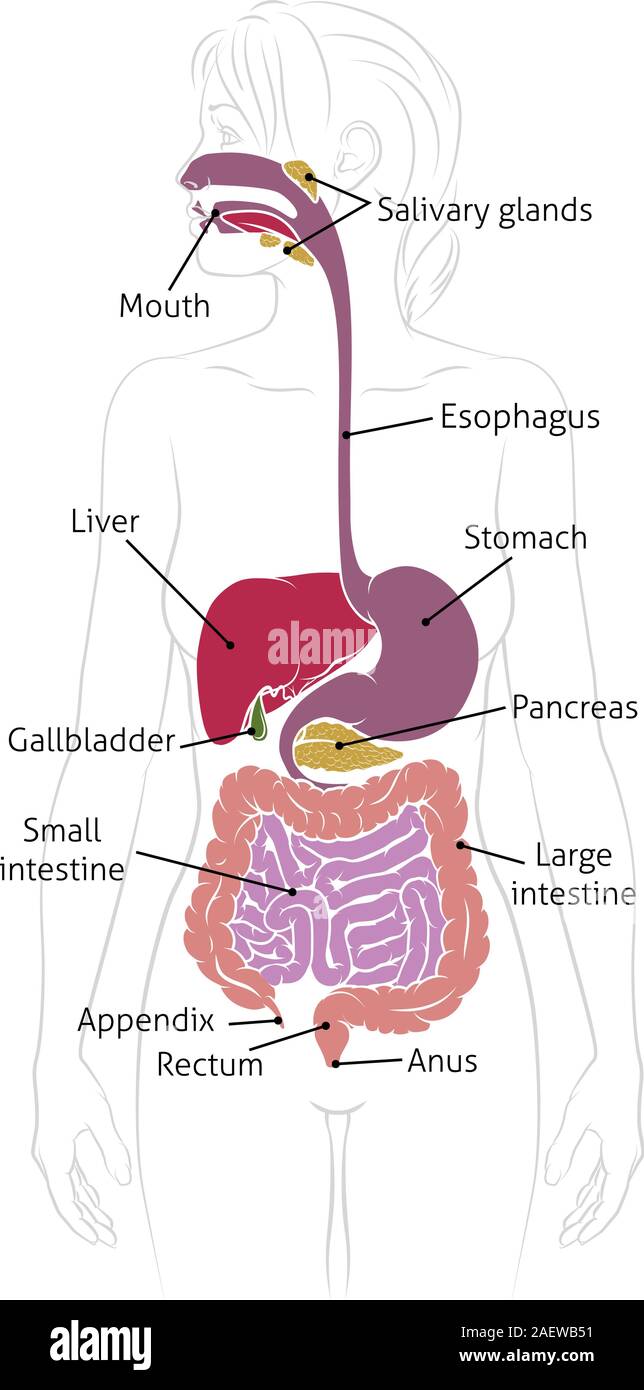

Système digestif humain Femme Schéma anatomique Illustration de Vecteurhttps://www.alamyimages.fr/image-license-details/?v=1https://www.alamyimages.fr/systeme-digestif-humain-femme-schema-anatomique-image336159741.html

Système digestif humain Femme Schéma anatomique Illustration de Vecteurhttps://www.alamyimages.fr/image-license-details/?v=1https://www.alamyimages.fr/systeme-digestif-humain-femme-schema-anatomique-image336159741.htmlRF2AEWB51–Système digestif humain Femme Schéma anatomique